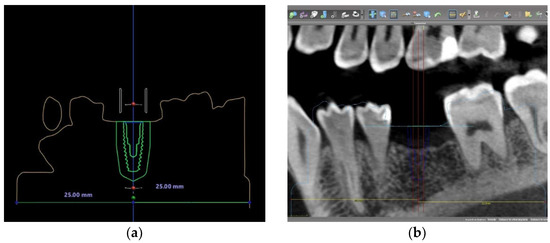

2.2. Implant Position Planning Procedure in Three Different Software Programs

2.3. Surgical Guide Design and Fabrication in Three Different Software Programs